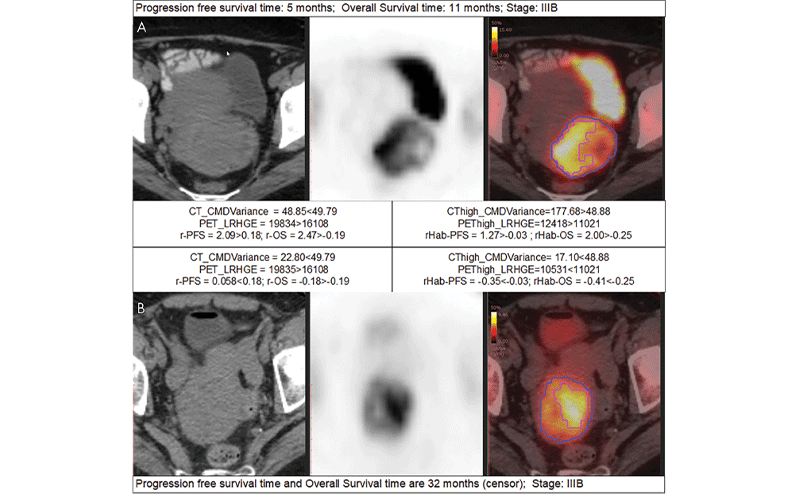

Examples of detailed radiomics signatures. A, B, are the CT, PET, and fusion images of two patients at the same stage but with bad prognosis (progression-free survival [PFS] of 5 months, overall survival [OS] of 11 months, and stage IIIB) and good prognosis (PFS of 32 months, OS of 32 months, and stage IIIB), respectively. The red contours in the fusion images indicate the high metabolic habitat, while the rest of the region in the blue contour is the low metabolic habitat. The cutoffs (49.79, 16108, 48.88, 11021, 0.18, −0.19, −0.03, and −0.25) are obtained using X-tile software on the training dataset. The larger the radiomics signatures (r-PFS, r-OS, rHabPFS, and rHab-OS), the higher the risk of progression or death. CMDvariance = difference variance feature calculated from co-occurrence matrix, LRHGE = long run high gray-level emphasis calculated from run-length matrix, r-OS = radiomic signature for OS obtained with PET plus CT features, r-PFS = radiomic signature for PFS obtained with PET plus CT features, rHabOS = radiomic signature for OS obtained with PET plus CT plus habitat features, rHab-PFS = radiomic signature for PFS obtained with PET plus CT plus habitat features.

Mu et al, Radiology: Artificial Intelligence 2021 ©Radiology: Artificial Intelligence 2021